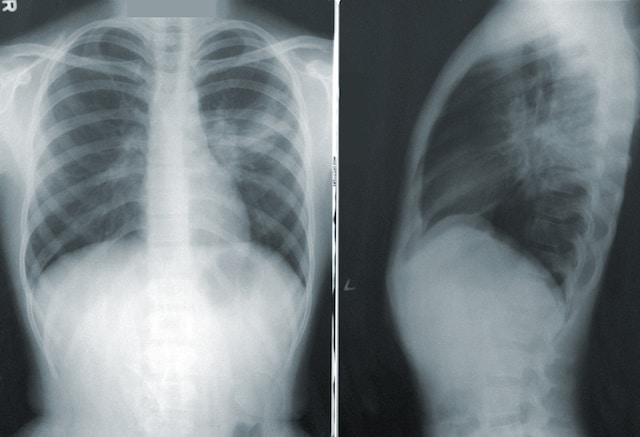

폐렴은 기관지 아래의 폐 조직이 박테리아나 바이러스에 의해 염증을 일으키는 전염병입니다. 감염은 폐의 작은 기낭(폐포)으로 들어갑니다. 폐렴은 폐의 기도(기관지) 감염과 다릅니다. 기도 감염을 기관지염이라고 합니다. 흉부 X-레이는 폐렴을 암시하는 소견을 보여줍니다. 폐렴에 걸린 경우

폐렴은 증상과 징후 및 배양 검사 결과에 따라 진단할 수 있습니다. 그러나 증상은 종종 사람마다 다릅니다. 세균 배양은 정확하게 진단할 수 있지만 세균 배양은 폐렴 사례의 약 50%에서만 시행됩니다. 정확한 진단을 위해 흉부 엑스레이를 촬영합니다. 가래검사, 혈액검사, 혈청검사, 흉수배양검사를 시행할 수 있습니다. 치료에 있어서는 주사제나 경구용 항생제를 투여하는 것이 중요합니다. 증상이 심하지 않으면 외래 진료를 받는다. 매우 어리거나 매우 나이가 많고 암과 같은 또 다른 심각한 건강 문제가 있고 매우 심각한 폐렴이 있고 호흡 곤란과 같은 심각한 증상을 겪고 있는 사람들은 입원합니다.